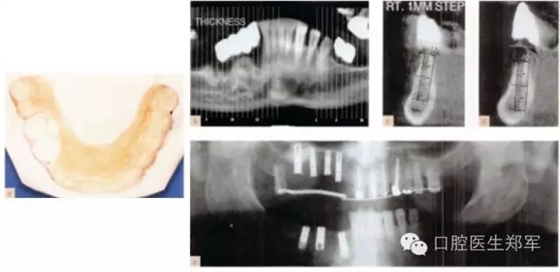

圖10 a 下頜影像和外科導(dǎo)板。b-d 下頜CT中放射導(dǎo)板的位置 e 種植后的影像圖片 |

圖11 a和b 種植體基臺和基牙的預(yù)備。c 再次評估暫時修復(fù)體并確認(rèn)其功能、美學(xué)和穩(wěn)定性。d根據(jù)回切硅膠導(dǎo)板和暫時修復(fù)體交叉上牙合架技術(shù)修整最終修復(fù)體蠟型。 |

圖12 a和b最終修復(fù)體(圖由修復(fù)學(xué)專家Dr 0 Gelfan, Professor Z Artzi , and Mr B lndig.提供) |